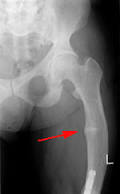

Para o diagnóstico de osteomalácia deve-se realizar alguns exames como raio-x, densidade mineral e avaliação da concentração de cálcio, fósforo e vitamina D no organismo.